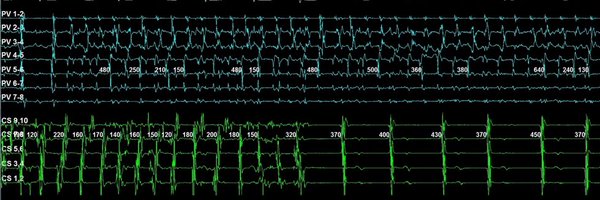

I just had a revelation: all American electrophysiologists should be required to spend 2-4 weeks doing ablation cases in Europe before finishing training

#ESCCongress πŸ‡ͺπŸ‡Έ LBCT Nanosecond PFA (n=142) vs AI-guided RFA (n=145) in paroxysmal #AFib - insightPFA trial πŸ‘‰12-month success rate: 67.7% vs 67.4%; HR 0.99 (0.66-1.47) πŸ‘‰No procedure related serious adverse events in both groups Can PFA be faster? Apparently yes β€” and seems to